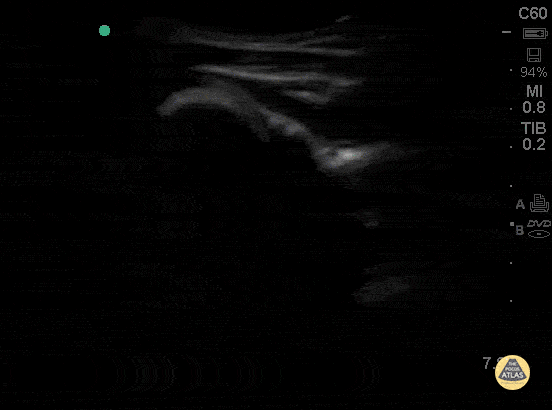

This clip of the shoulder is obtained by placing the probe in transverse plane on the posterior shoulder, and demonstrates the humeral head (left of screen) rotating in the glenoid. The scapular spine is to the right of the glenoid. The infraspinatus muscle is seen overlying the humeral head superficial to the infraspinatus is the deltoid muscle. Hannah Kopinksi and Dr. Lindsay Davis - NYU Emergency Medicine